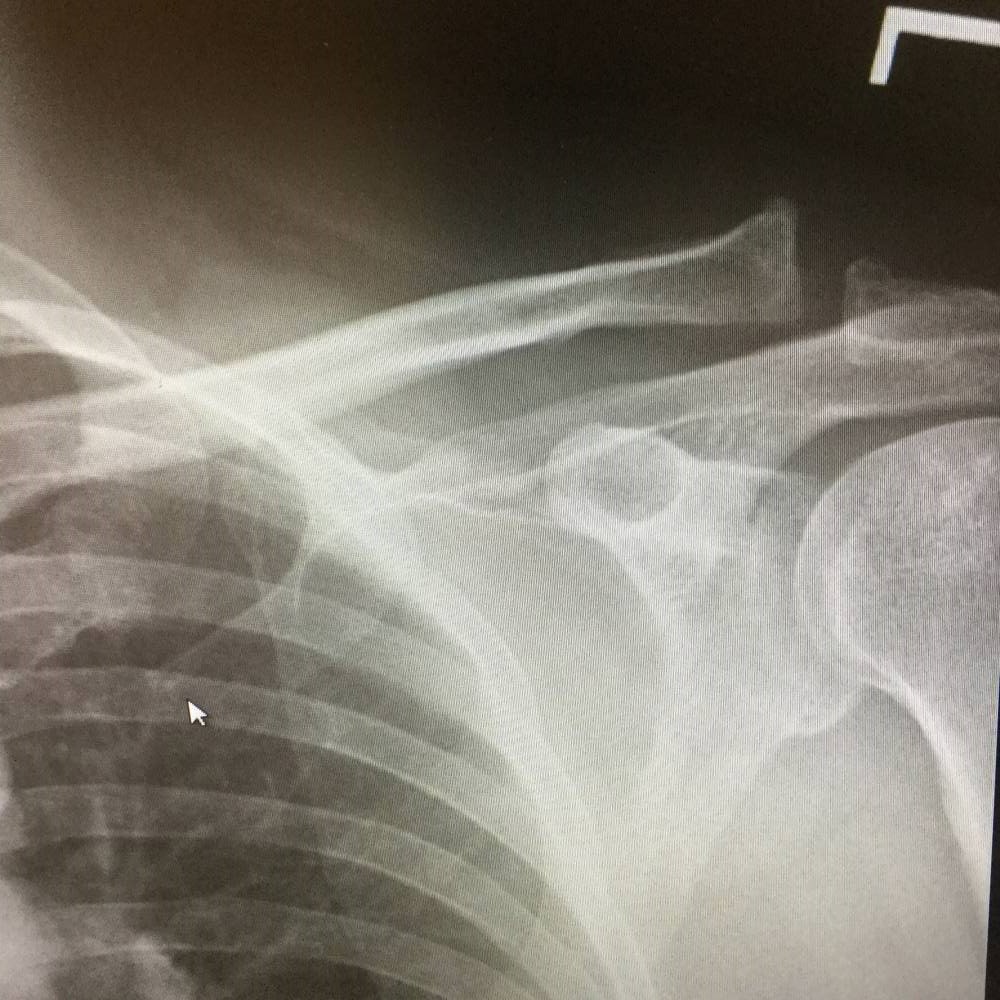

Hey Scott, sorry again about this but it was straight over the handlebars ... just thrilled I could get up and walk.  It is some connective tissue

separation that may or may not need surgery.  Many weeks off from just about everything.

MRI today and consult on Tuesday but do not want to let this kite sit for the Fall/Winter if someone can enjoy it.